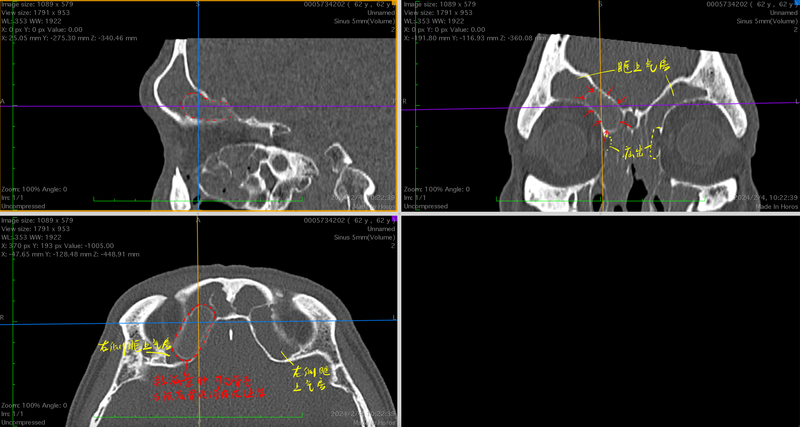

一例復(fù)發(fā)性全組鼻竇炎伴鼻息肉的患者

10年前在外院接受了全麻鼻竇炎手術(shù),術(shù)后癥狀短暫緩解,2年后再次復(fù)發(fā)。于我院就診時有明顯鼻堵、黃涕、嗅覺下降,并伴有間斷頭部悶脹感,自覺頭暈。術(shù)前CT發(fā)現(xiàn)除雙側(cè)嚴(yán)重全組鼻竇炎外,還伴有雙側(cè)眶內(nèi)壁的廣泛缺損,可能與既往外傷史或手術(shù)史有關(guān)。同時發(fā)現(xiàn)右側(cè)額篩區(qū)域黏液囊腫形成,同樣可能與既往手術(shù)時此區(qū)域開放不完全有關(guān)。此次手術(shù)我們采取鼻內(nèi)鏡下根治性手術(shù)(鼻竇輪廓化)+Draf3型額竇手術(shù)的術(shù)式,旨在充分開放所有鼻竇氣房,去除不可逆病變,尤其是可能導(dǎo)致疾病反復(fù)發(fā)作、發(fā)展的病骨,術(shù)中需要特別注意辨識并保護(hù)雙側(cè)眶內(nèi)壁骨質(zhì)缺損的位置,最終術(shù)中我們將雙側(cè)眶疝出的部分進(jìn)行了充分的輪廓化,并去除了其上方的眶上氣房、篩前動脈骨管周圍的病變。圍手術(shù)期除常規(guī)抗感染、促排、沖洗等用藥外,增加口服激素的序貫治療?;颊咝g(shù)后恢復(fù)良好,于術(shù)后第3天出院,無相關(guān)并發(fā)癥出現(xiàn)。